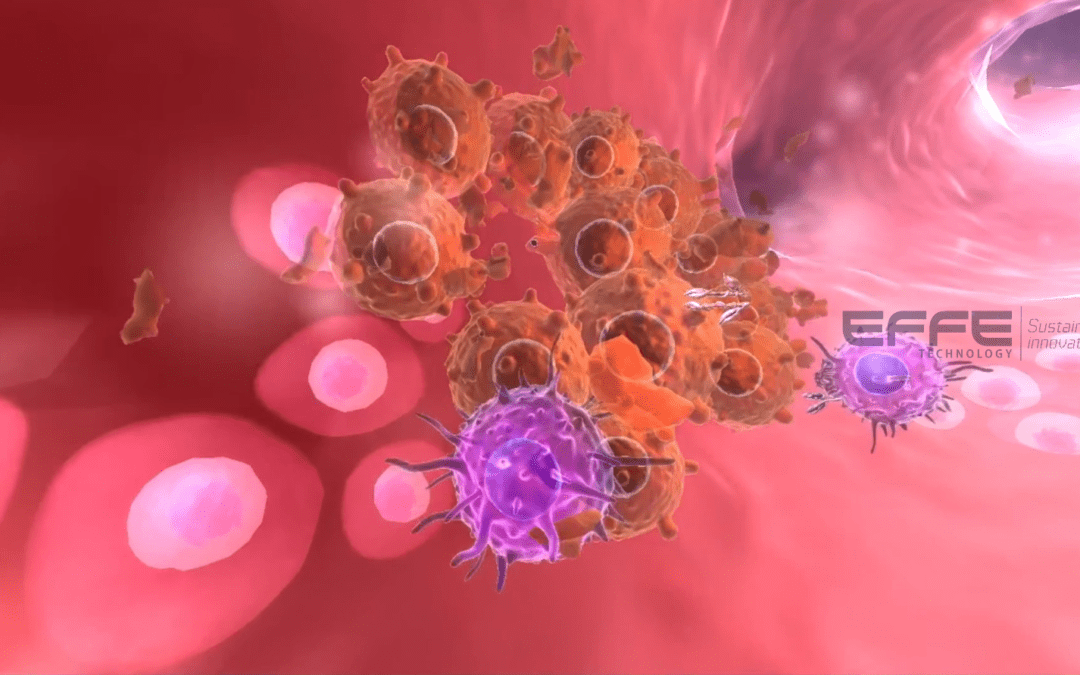

Overview Immunotherapy has transformed modern oncology, yet explaining immune mechanisms, checkpoint pathways, and...

Overview Immunotherapy has transformed modern oncology, yet explaining immune mechanisms, checkpoint pathways, and...